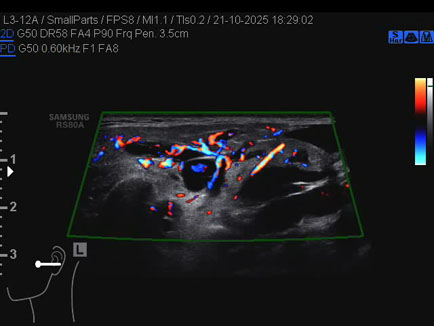

Ecografia del: 21/10/2025

Strumento: Samsung

Sonda: Lineare

Età Paziente: 50 anni

Commento all'esame: 50enne con stenosi del dotto di Stenone sn ed ectasia del dotto medesimo a dx.

Conclusioni: stenosi del dotto di Stenone sinistro (left Stensen's duct stenosis).